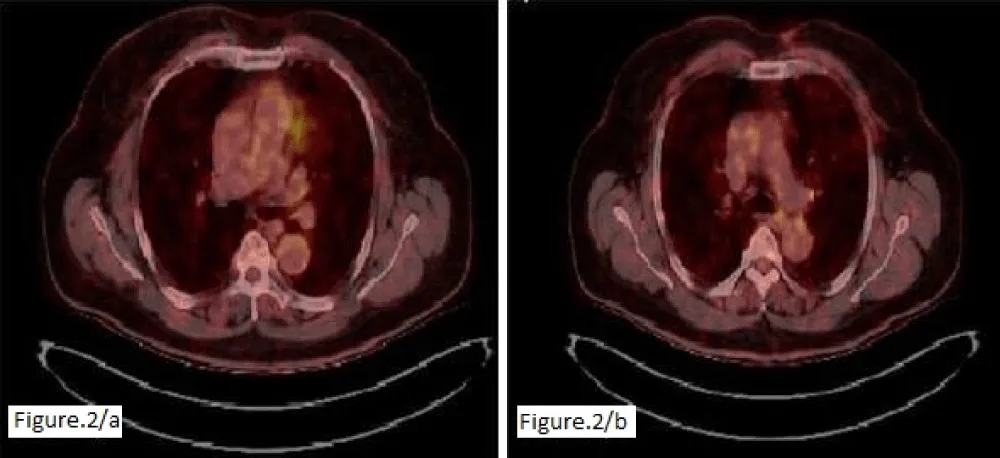

A 65-year-old man presented to the dermatology clinic with complaints of a large erythematous plaque on the anterior chest that had been gradually increasing for two months. He had a history of gout, hypertension, and inflammatory bowel disease, and a history of renal cystectomy and lumbar disc herniation. A biopsy revealed atypical lymphoid infiltration consistent with CD5-negative non-Hodgkin’s B-cell lymphoma, with diffuse CD20 positivity, focal BCL-6 and CD10 positivity, and negative CD34, CD117, TDT, and p63 positivity, extending from the superficial dermis to the subcutaneous fat. The patient was referred to the hematology department. The patient, who had no symptoms, had a PET-CT scan of the left hemithorax. A 57 x 74 mm irregular mass infiltrating the skin/subcutaneous tissue and bilateral (prominent on the left) multifocal skin thickening reaching approximately 9 mm on the anterior chest wall was observed (Figure 1). No systemic involvement was detected, and the patient was referred for RT without considering chemotherapy, phototherapy, or cryotherapy. The patient was treated with the Linac device using an intensity-modulated RT technique using 6 MV photon energy. A boost of 30 Gy/17 fractions was applied to the extensive lesions on the anterior chest wall, and a boost of 20 Gy/11 fractions was applied to the primary mass. Post-treatment physical examination revealed marked regression of the mass and disappearance of the erythematous lesions. A one-month CT scan revealed marked regression of the primary mass and a complete response in the smaller lesions. Six months later, the lesions were reported to have completely disappeared (Figure 2).

Figure 1: Intense hypermetabolic activity corresponding to irregular areas of thickening with focal nodular formations in the cutaneous tissue of the anterior chest wall, more prominent on the left side.